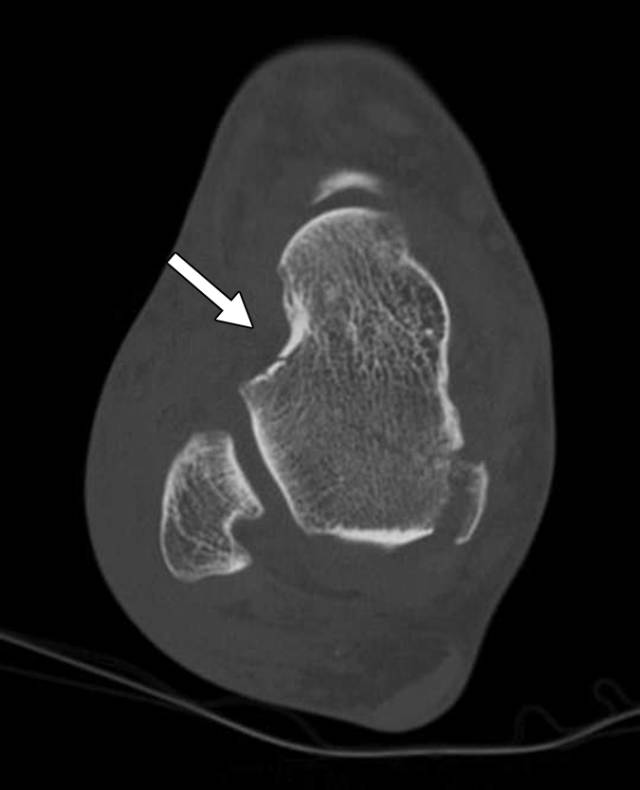

怎么取放射片研究--浅析下肢创伤中容易漏诊的X线片_https://www.jmylbn.com_新闻资讯_第15张

怎么取放射片研究--浅析下肢创伤中容易漏诊的X线片_https://www.jmylbn.com_新闻资讯_第16张

图5 -53岁男性骨折骨折。C,随后的矢状(C)和轴向(D)CT图像更全面地显示通过延伸到距下关节的距骨的身体的另外的倾斜骨折(箭头)。